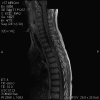

Representative images from the MR studies and specimen are illustrated below:

A. T1 |

B. T1+Contrast |

C. T1+Contrast |

D. T2 |

E. T1+Contrast |

Panel A to E are MR images. Panel F and G are taken from intraoperative cytologic preparation. Panel H to M are taken from frozen section. Panel N and O are from paraffin section. These sections are stained by hematoxylin-eosin stain. Panel P is immunohistochemistry for neurofilament proteins. Panel Q is stained by Luxol fast blue-Periodic acid Schiff (LFB-PAS) stain.

The segment of spinal cord at T3-T4 level is expanded and is accompanied by edema that runs from T2-T6. The expansion and edema is roughly symmetrical along the long axis of the cord. The expanded levels are isointense to the white matter of the spinal cord on T1-weighed images (Panel A). The edema is best demonstrated on T-weighed images (Panel B, C, and E). Patchy and poorly defined enhancement is demonstrated in the expanded areas (Panel D). The remaining levels of the spinal cord and the brain are free of abnormal changes.